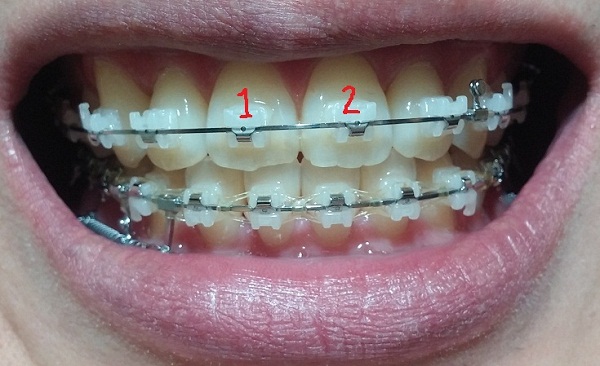

치료내용

-하악 파워체인 엇갈려서 걸어놓기(후기 23화와 같은 치료),

-하악 스프링 + 덧대기(잇몸이 눌리지 않게)

-고무줄착용하기(전 치료와 동일)

현재 교정진행상태

-중심선 99% 맞은 상태!!

-하악 파워체인으로 치아끼리 꽉 조여서 마무리로 가는 중!!

-일회용 고무줄로 치아를 다물 때, 뜨는 공간이 없게

상악 송곳니와 하악 송곳니를 당기는 중!!

[정면]